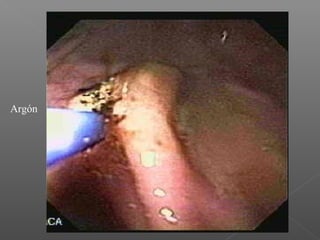

II. Métodos térmicos

Se basan en la aplicación de calor para el logro de la hemostasia.

No contacto

Argón plasma

Dieulafoy

Argón

Angiodisplasia